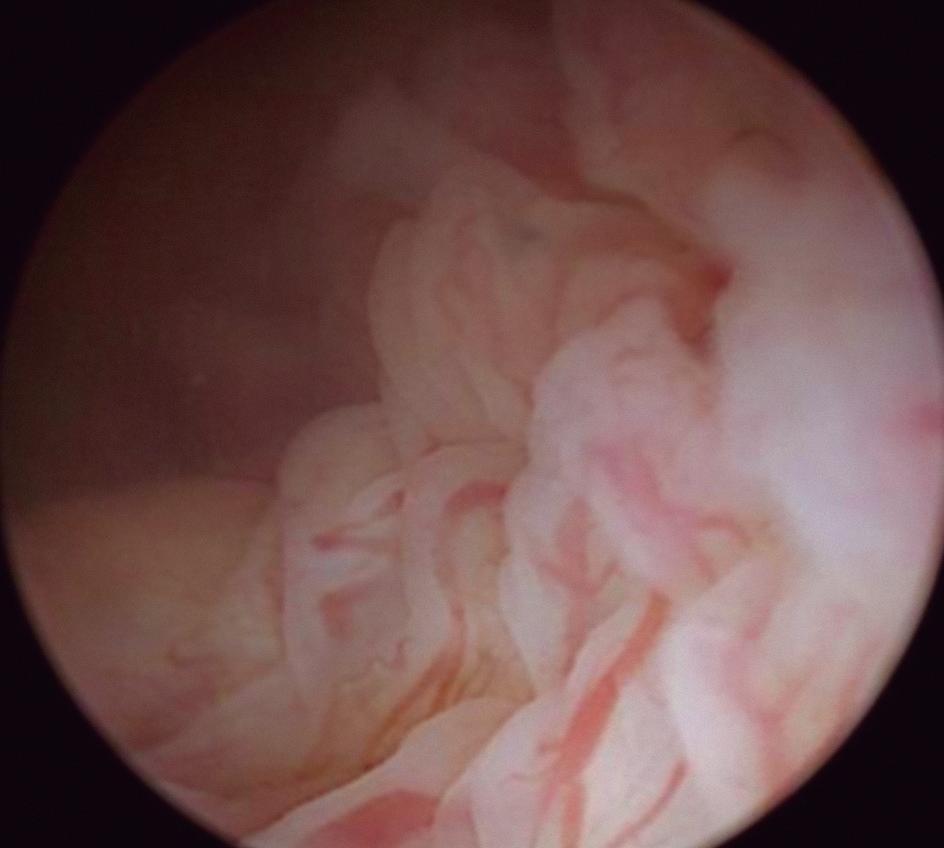

Endométrio Menstrual

Costuma ter superfície irregular com áreas hemorrágicas, intercaladas por placas endometriais esbranquiçadas (Fig. 1-20).

Fig. 1-20. (a-f) Diversas imagens do endométrio menstrual. (Fonte: arquivo pessoal do autor.) (Continua)